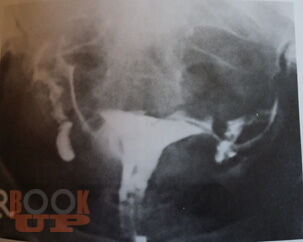

В пособии представлены данные об этиологии, современных методах диагностики и лечения бесплодия в браке. Подробно изложен алгоритм обследования супружеской пары на различных этапах постановки диагноза, тактика ведения пациенток. В результате использования учебного пособия студенты могут овладеть следующими компетенциями: ОПК 8, 11, 12; ПК 1, 5, 6, 8, 9, 10. Предназначено для использования в учебном процессе студентов старших курсов по специальностям: «Лечебное дело», «Педиатрия», «Медико-профилактическое дело».